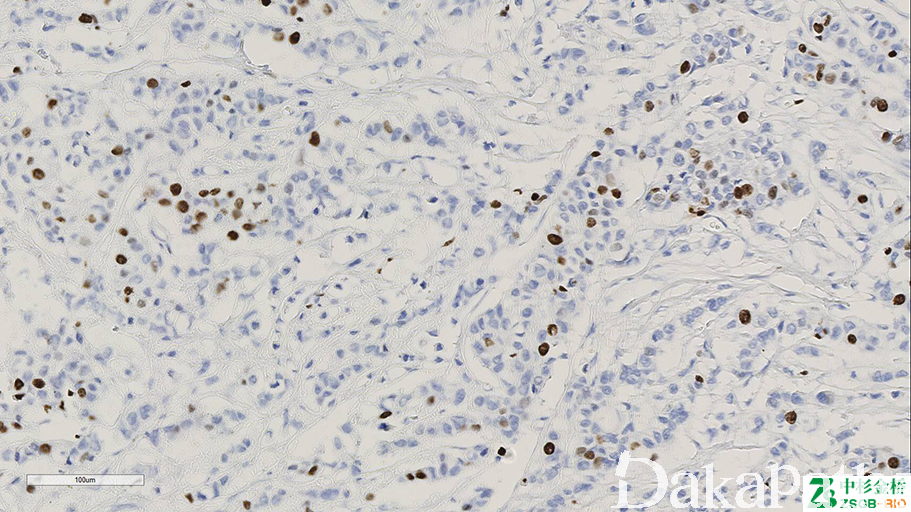

Ki-67

标记处于细胞周期 G1,S,M,G2 期的细胞,G0 期细胞阴性。用于肿瘤细胞增殖评价。

信号定位: 胞核